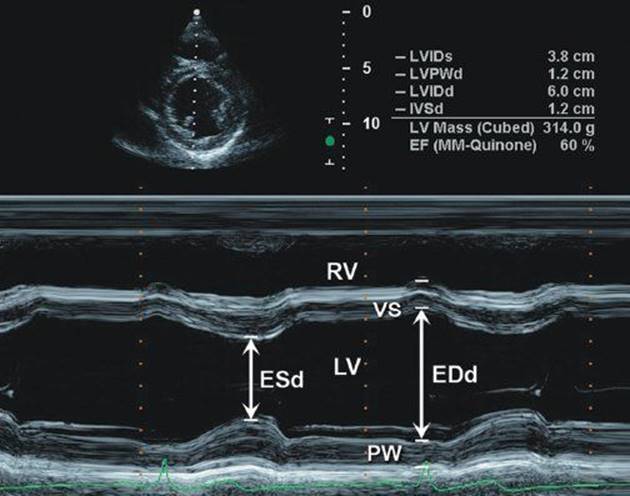

نارسایی قلب

نارسایی قلبوظیفه قلب رساندن خون تمیز و پر از اکسیژن و غذا به همه جای بدن است. اگر به هر دلیلی قلب نتواند این کار را انجام دهد، دچار نارسایی عملکرد شده و بیماری "نارسایی قلب" ایجاد می گردد. نارسایی قلب بیماری بسیار مهمی است که تقریبا بر عملکرد تمام ارگان های بدن می تواند آسیب برساند. این وبلاگ با هدف آشنایی بیشتر با علائم و درمان های این بیماری ایجاد شده است.